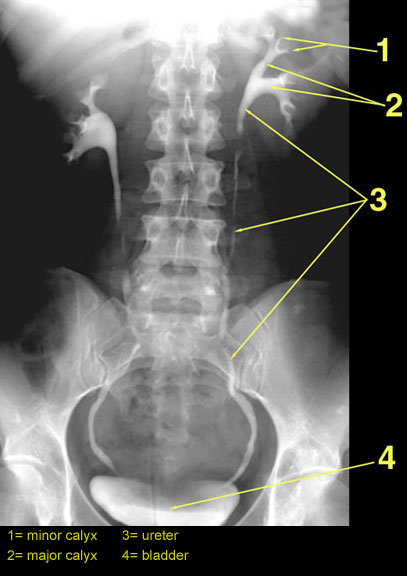

The image on the left is a normal IVP. The image on the right shows an IVP with contrast leak.